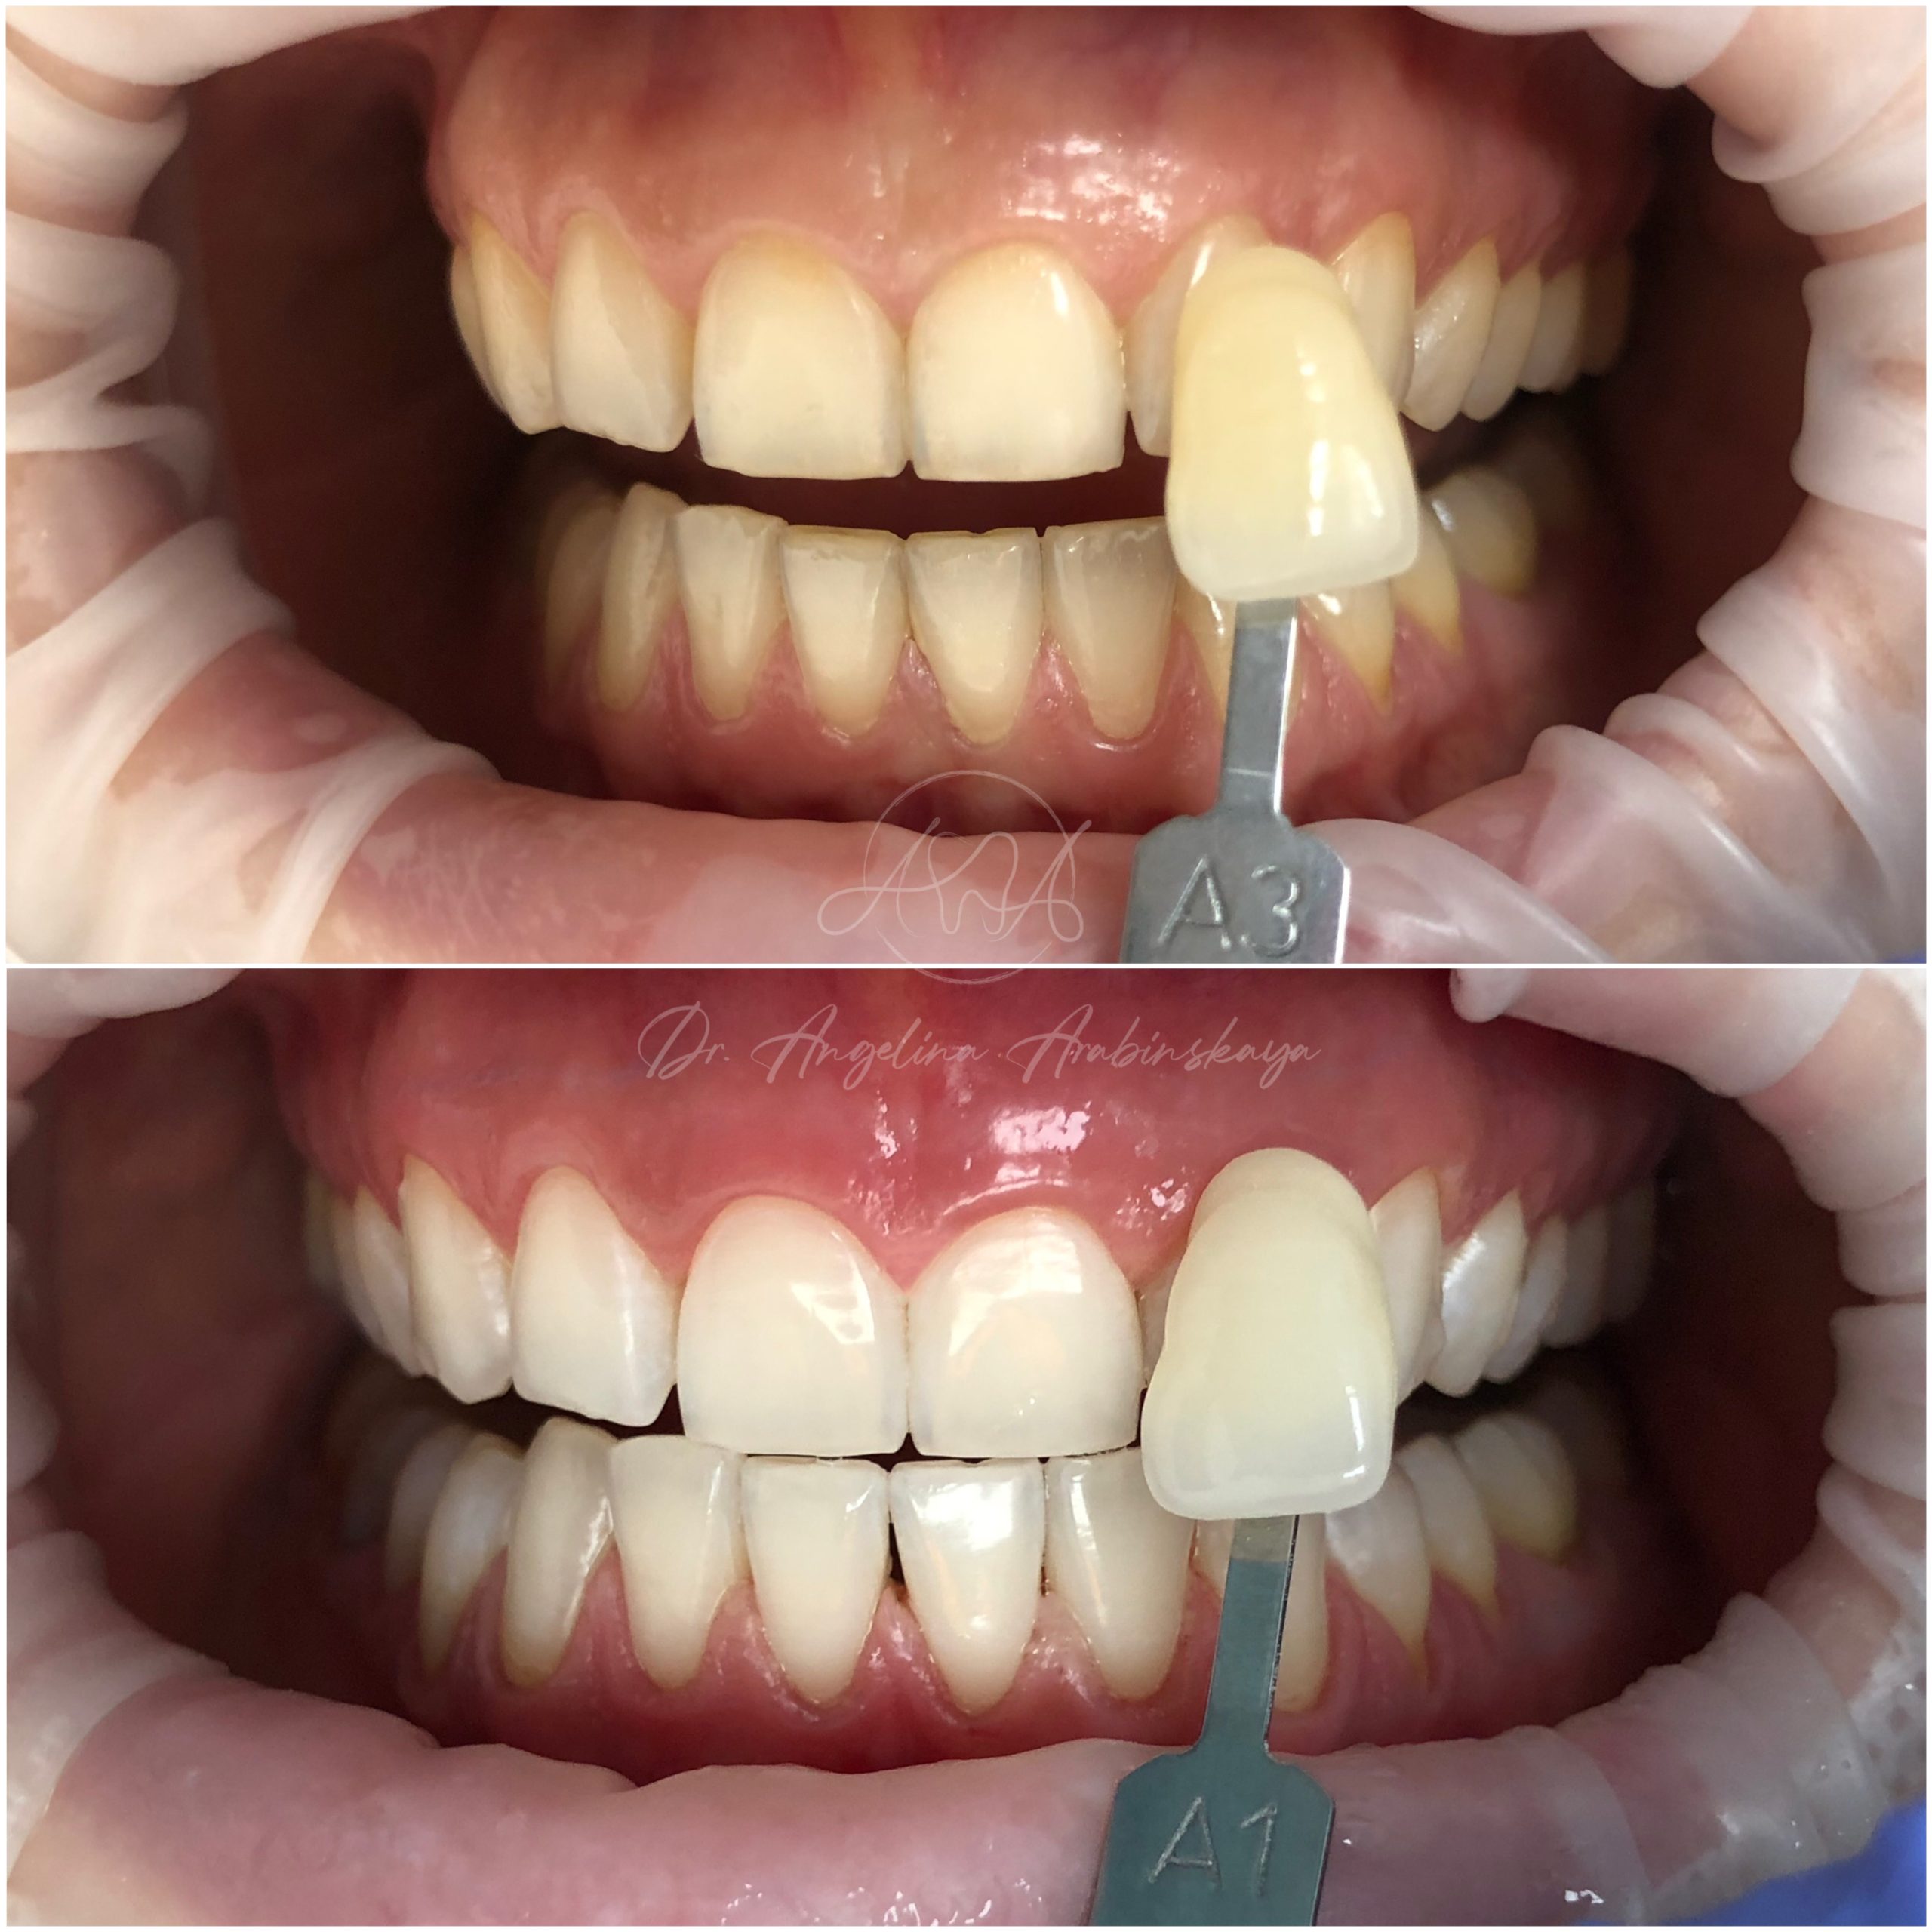

• Профессиональная отбелка зубов системой ZOOM,BEYOND

• Домашнее отбеливание зубов